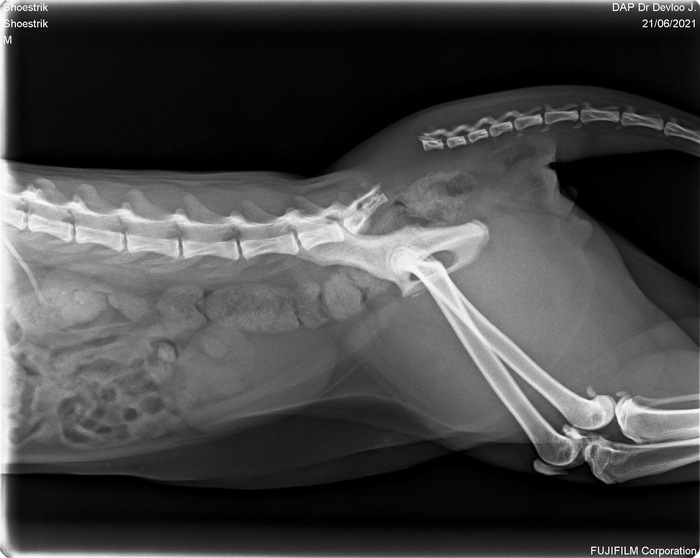

Никто не готовился к тому, что в два года его позвоночник будет сломан. Мы так и не узнали кто это сделал. Хвост был просто оторван, вряд ли он сам себя так повредил.

“Шансов три процента.” - вот что мы услышали в клинике.

Вот в принципе понятно что было с котиком